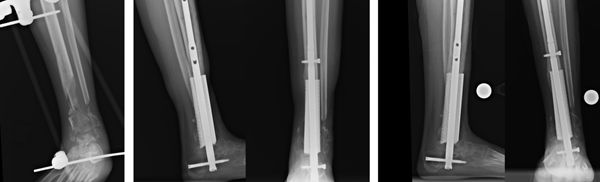

幾年前,Gall負(fù)責(zé)為一名年輕患者設(shè)計(jì)和打印定制的鈦植入物,該患者在車禍中小腿骨骼嚴(yán)重受損。杜克大學(xué)整形外科醫(yī)生塞 Samuel Adams解釋說:“當(dāng)時患者的情況非常危機(jī),患者已大量骨質(zhì)流失,我們沒像其他醫(yī)院一樣給患者進(jìn)行截肢,而是在患者體內(nèi)植入一個3D打印的植入物代替丟失的骨頭?!?/span>GallAdams 合作,使用患者的CT掃描進(jìn)行支架的制造和設(shè)計(jì),以支撐患者體重的同時在鈦結(jié)構(gòu)周圍愈合和生長新骨。經(jīng)過分析,他們設(shè)計(jì)了一塊4英寸的多孔固體鈦替代患者受損的脛骨遠(yuǎn)端。

Gall指出腿部或腳踝植入物的挑戰(zhàn)在于,它們必須在患者傷口愈合過程中起到承重作用的同時促進(jìn)骨骼生長;其他復(fù)雜的設(shè)計(jì)因素還包括植入物的外部形狀、每個患者的骨骼形狀,以及骨骼生長方式。

restor3d3D打印植入物取代了遠(yuǎn)端脛骨。圖片由杜克健康提供。